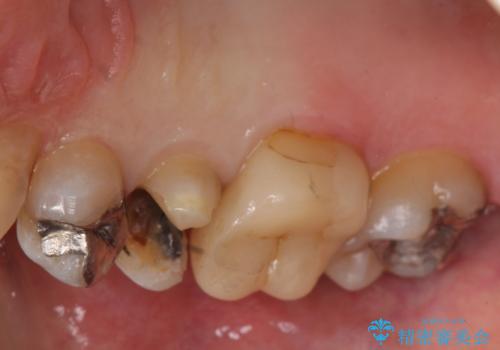

- 銀歯の下が虫歯になっていたため、虫歯を取り、セラミックインレーで修復しました。

見るだけでは、わかりにくいのでしっかりレントゲンを診てもらえるような定期検診が大事です。

銀歯が合っていないなどは、見た目だけではわかりにくいことがあります。

早めに見つけて、症状が出る前に治すことが大事です。

歯科医師にレントゲンをしっかり診てもらうことが重要です。